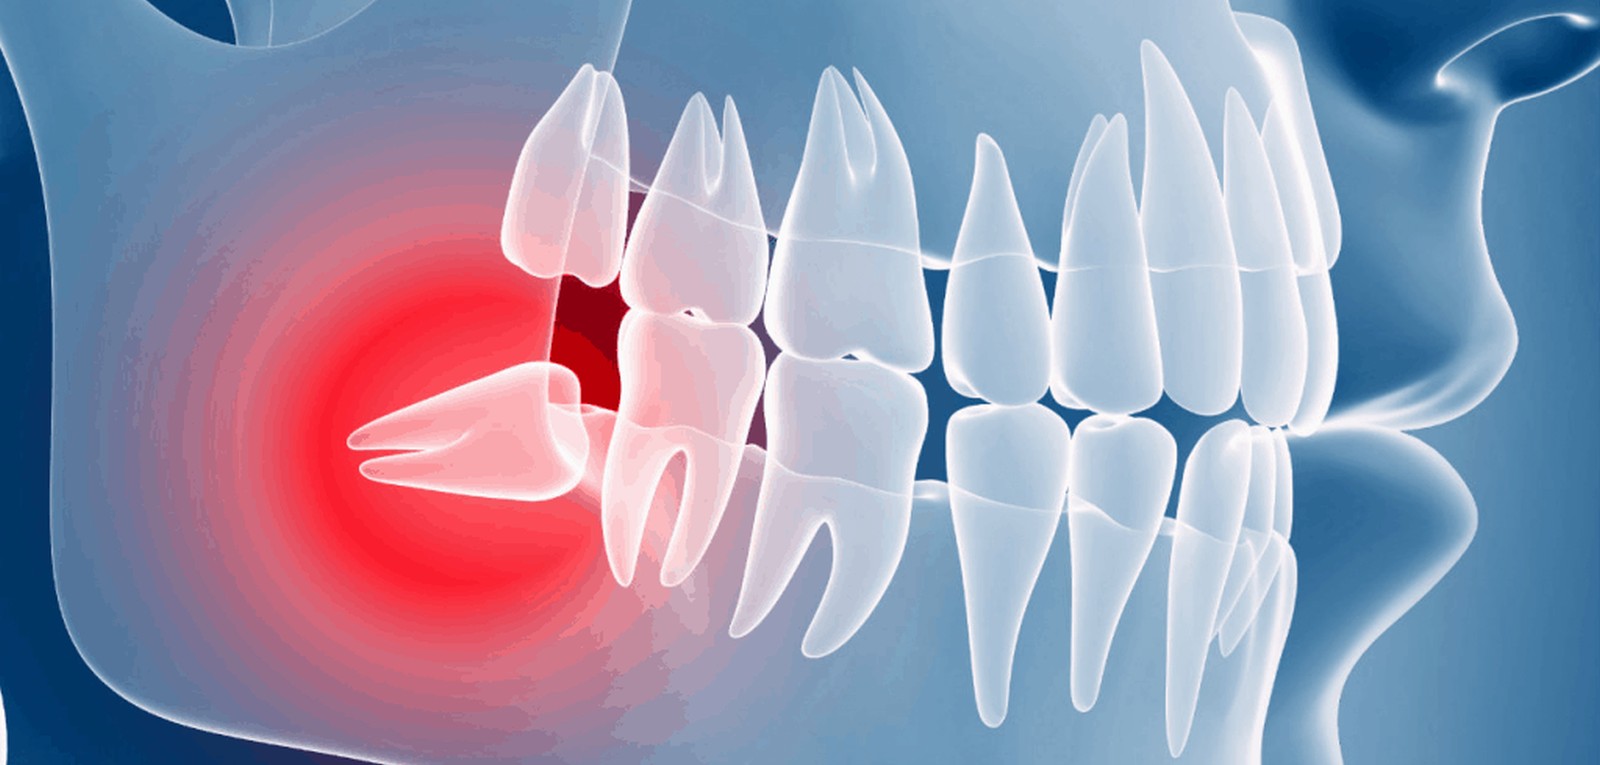

ينمو للعديد من الأفراد ضروس عقل متأثرة — ضروس لا يوجد لها متسع كافي لتنبثق داخل الفم أو لتنمو بشكل طبيعي. قد لا تنبثق ضروس العقل المطمورة (الدفينة) إلا انبثاقًا جزئيًا، أو لا تنبثق على الإطلاق.

- قد تنمو في زاوية باتجاه الأسنان المجاورة (الضرس الثاني)

مشاكل مع ضروس العقل المطمورة

من المرجح أن تحتاج إلى خلع ضرس العقل المطمور إذا نتج عنه مشاكل مثل:

- الألم

- تلف بسن قريبة أو العظم المحيطة بها